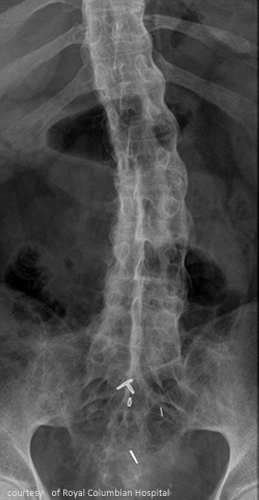

SI joint inflammation → fusion → ascends spine → complete spinal fusion (“bamboo spine”).

Radiographic signs of AS?

Early: SI joint blurring, narrowing; Late: “bamboo spine,” squared vertebrae.